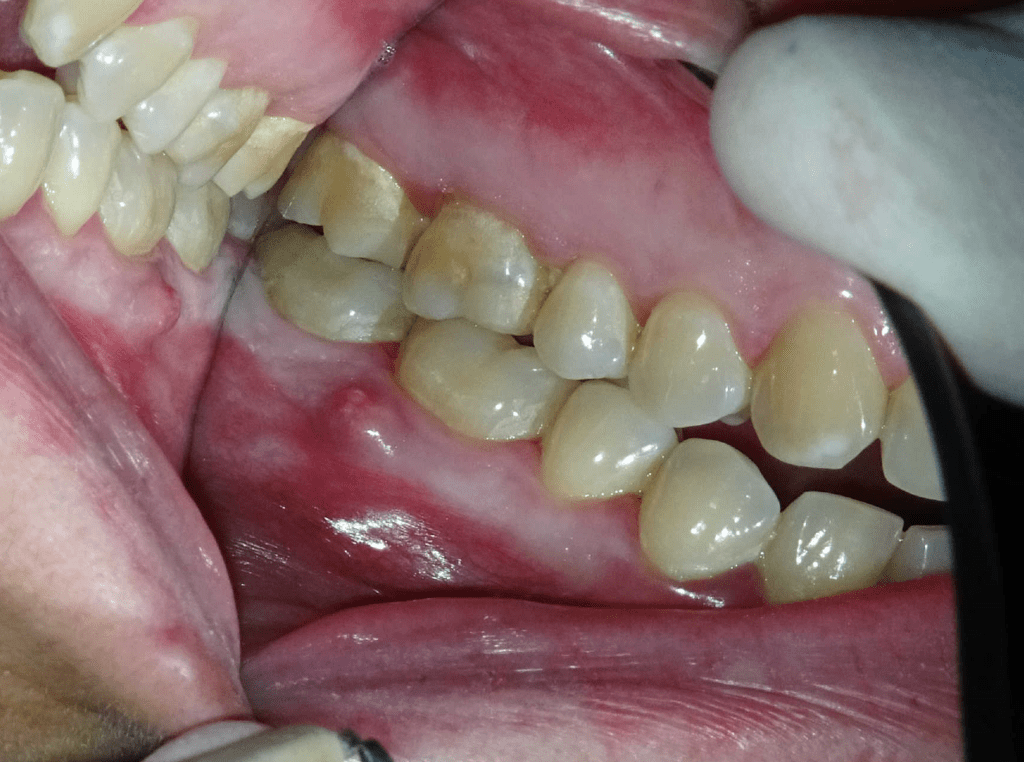

Fisura, remoción amalgama para explorar